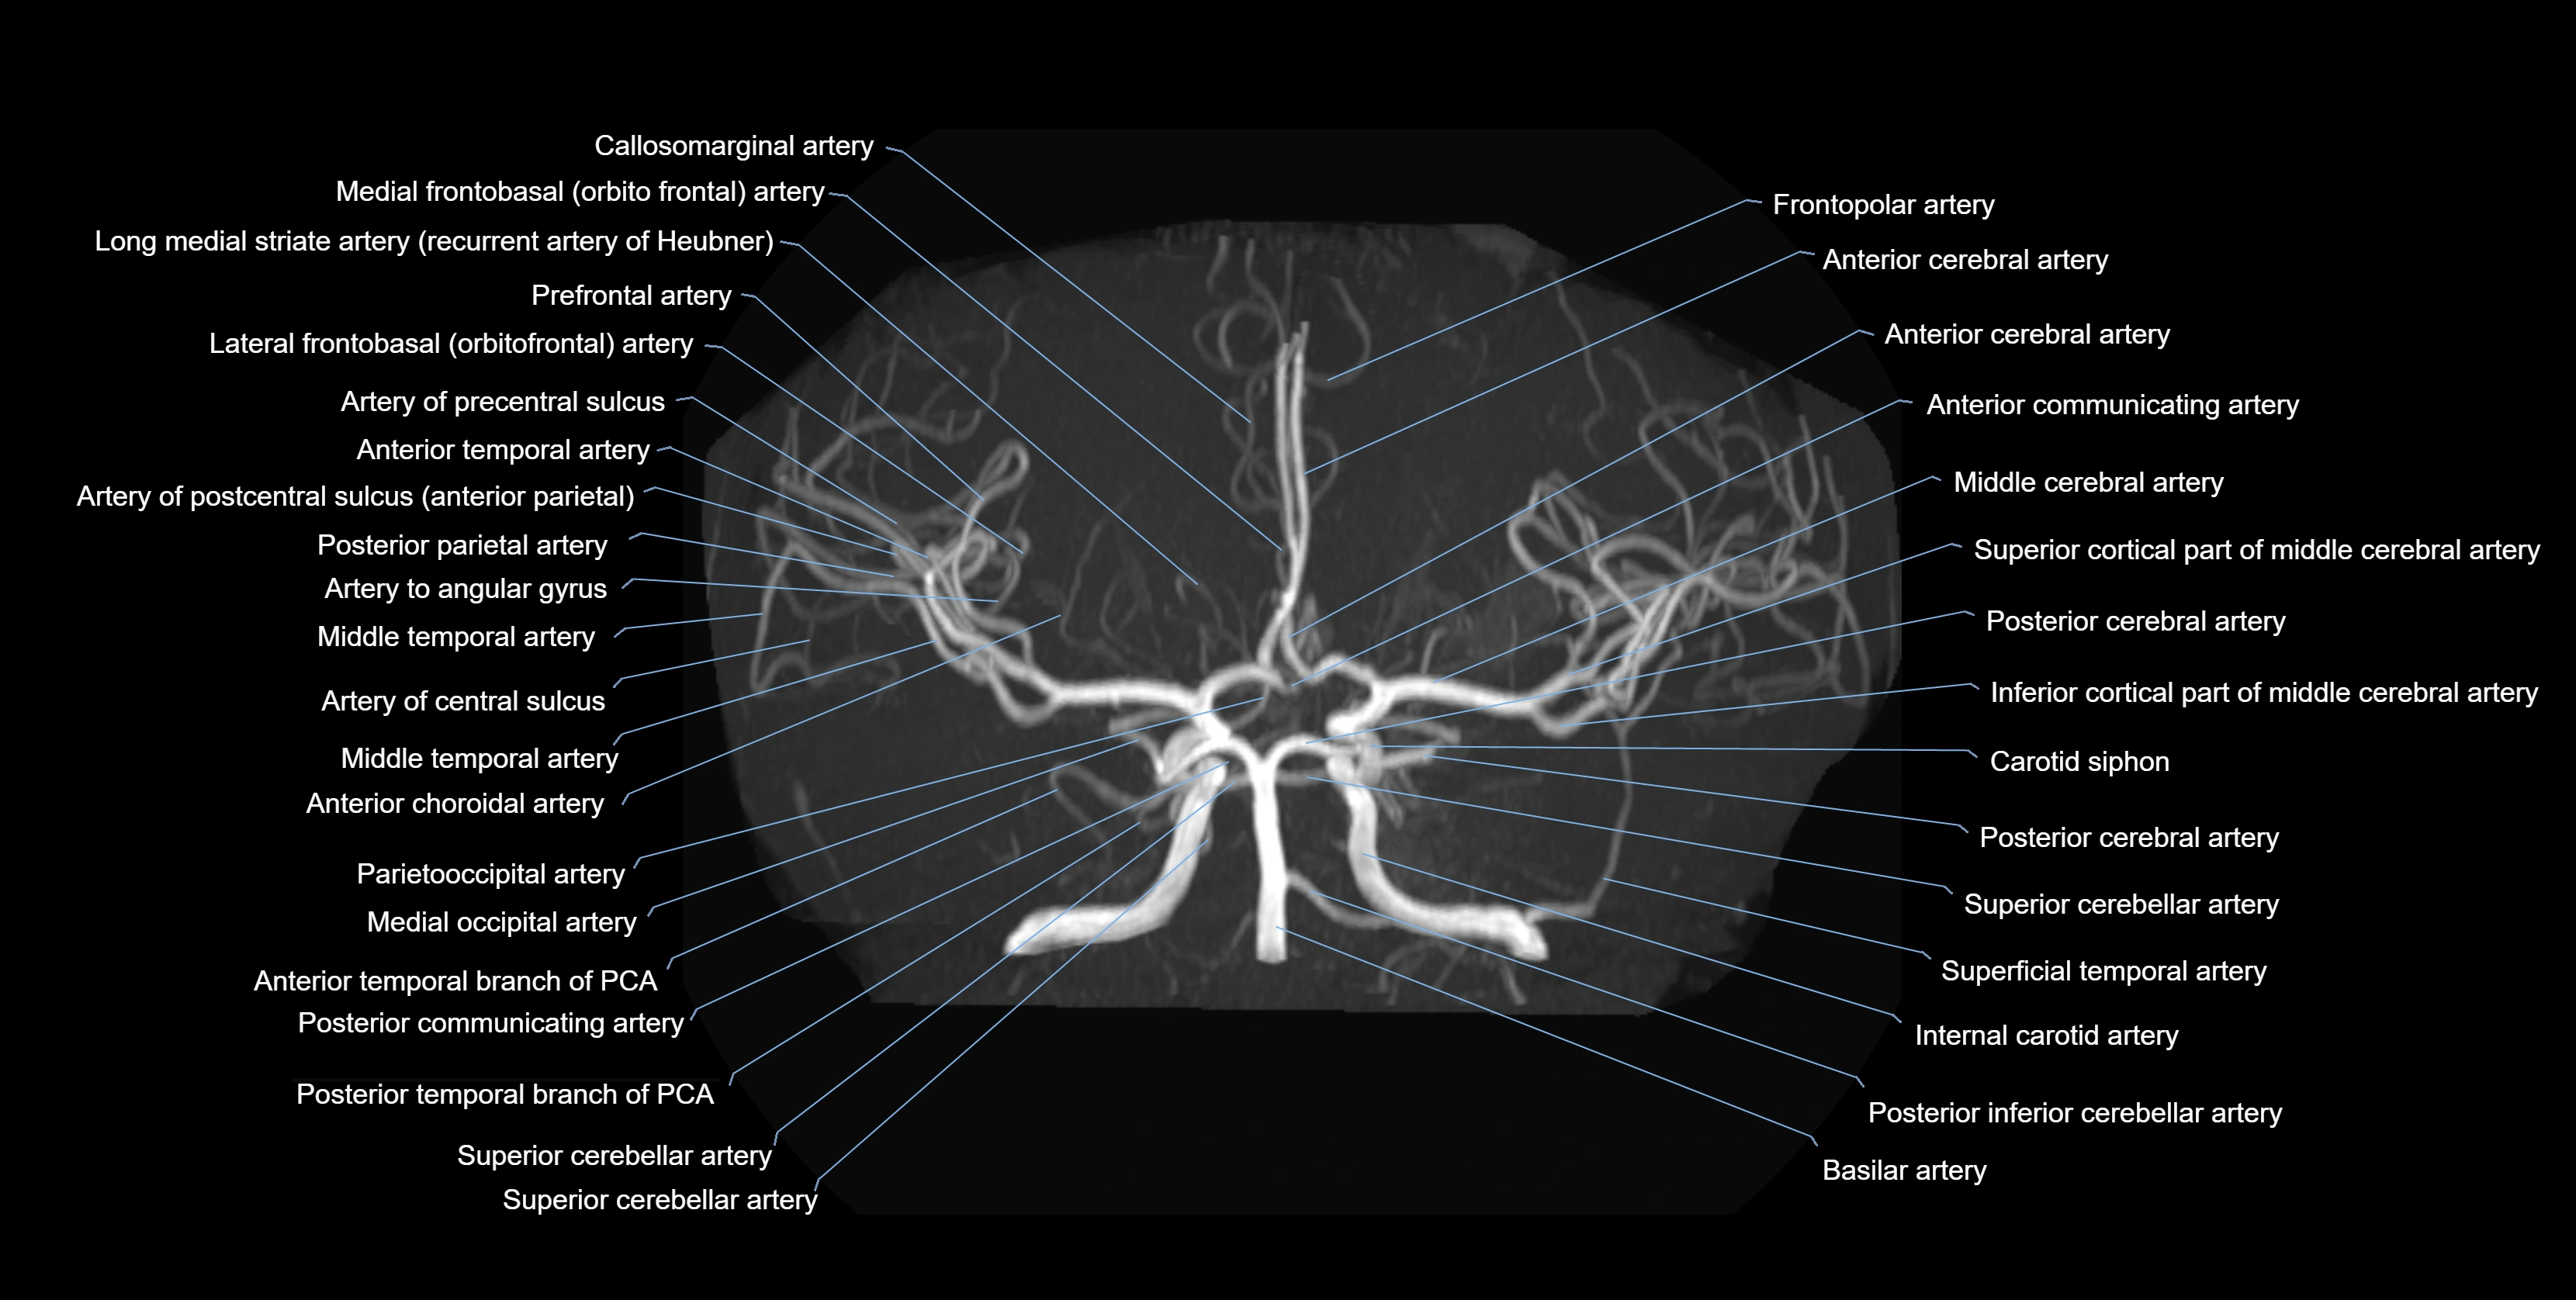

CTA (CT Angiography):

• Opacified with iodinated contrast, AChA appears as a bright high-attenuation vessel

• Visualized from ICA origin along optic tract toward choroid plexus

• 3D reconstructions depict its course and relation to adjacent arteries

• Gold standard for identifying aneurysms, occlusion, or vascular anomalies

CT images

image